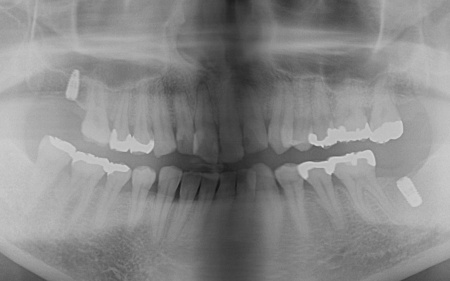

40代男性 虫歯治療やインプラント治療で口腔内全体を修復したあと部分矯正で噛み合わせを改善した症例

拝見したところ、複数の歯に虫歯が見られました。また、過去に治療した詰め物や被せ物が合わなくなっている部分や、歯が欠損している部位もあります。

・右上奥歯

一番奥の歯が欠損し、その手前の歯は詰め物の内部で虫歯が進行しています。

・右上前歯2本

虫歯が認められました。

・右下奥歯3本

噛む面や歯間に虫歯が見られ、歯が欠けている部分もあります。

・左上奥歯

一番奥の歯は、詰め物が合っていませんでした。また、詰め物が外れたままの歯もあります。

・左上前歯2本

虫歯や、被せ物の不具合が見られました。

・左下奥歯

一番奥の歯は虫歯が深くまで進行しており、歯の温存が難しい状態でした。さらに、その手前の歯2本は少し欠けています。

・前歯の噛み合わせ

下前歯が上前歯より前に出ている「反対咬合(こうごう)」で、将来的に歯や顎への負担が生じるリスクがあります。